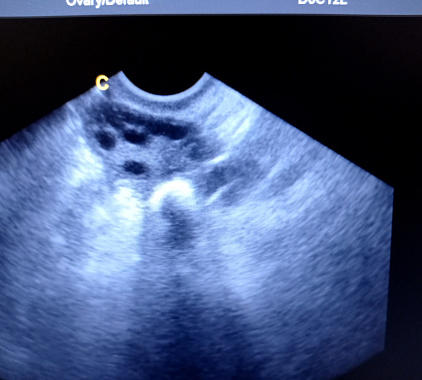

- фолликулы диаметром от 5 до 8 миллиметров, в середине цикла имеется доминантный фолликул диаметром 18–24 миллиметра;

УЗИ яичников показывает:

- поликистоз;

Что значит "фолликулы" в яичниках на УЗИ?

В норме во время ультразвукового исследования в яичниках присутствуют фолликулы. Они представляют собой структуры, в которых созревают яйцеклетки. Их наличие свидетельствует о том, что женщина способна зачать ребенка. Количество фолликулов влияет на шансы женщины забеременеть. Если есть 4–6 фолликулов, то риск зачатия низкий. Когда их количество от 7 до 12, процент зачатия высокий. Снижение фолликулов ниже 4 или увеличение более 16 подтверждает невозможность женщины забеременеть.